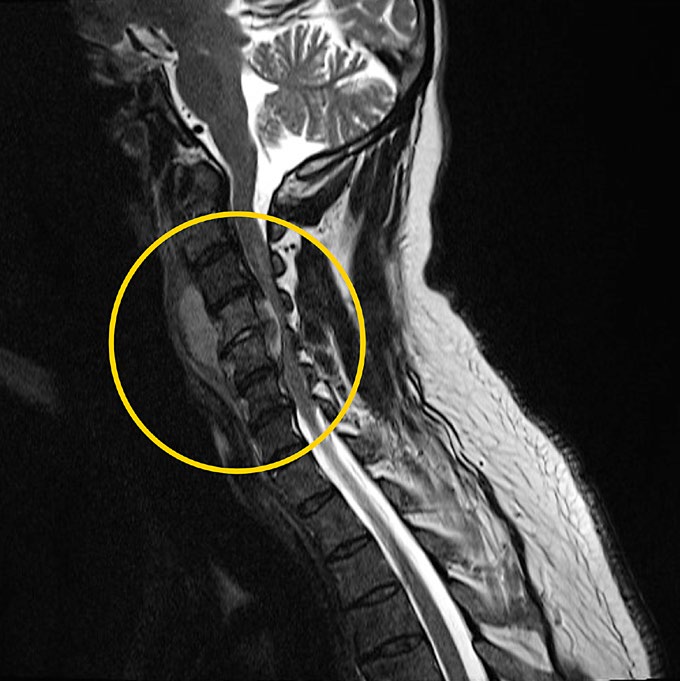

• Retropharyngeal Abscess with Extension to the Epidural Space: A Revealing Image of a Severe Complication

Sérgio Azevedo, Samba Baldé

111-112

DOI: https://doi.org/10.60591/crspmi.405